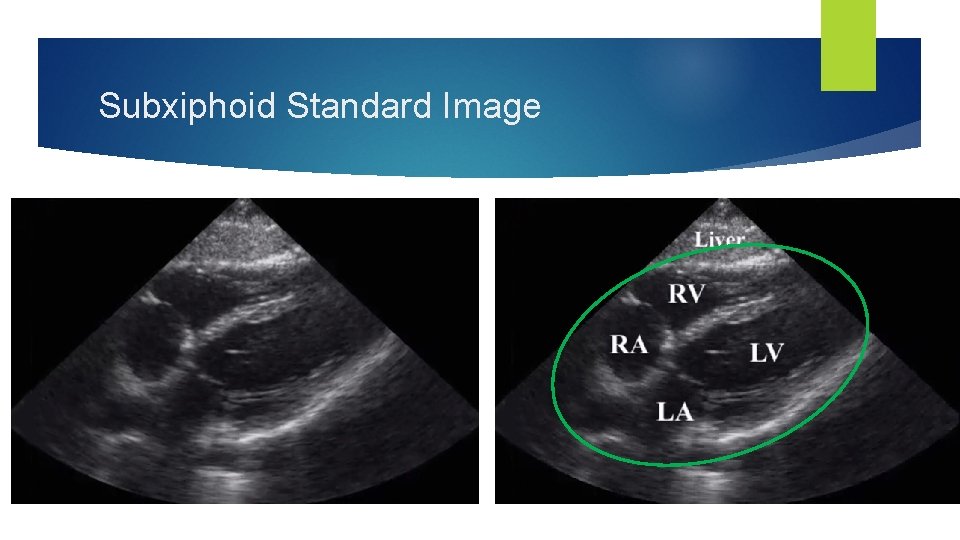

Subxiphoid Window Inferior to xiphoid process, angle towards head Transducer marker to patient's right

Subxiphoid View Scanning Tips Hold the probe like a computer mouse, allowing downward pressure with index and middle fingers Use the liver (a solid organ) as an “acoustic window” to avoid the stomach and poor visualization from air/gas Having the patient take and hold a deep breath in lowers the heart towards the probe, improving visualization

Subxiphoid Standard Image

Subxiphoid View in Motion Liver RV RA LV LA